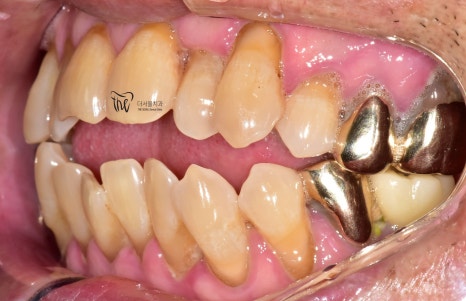

그리고, 오랜 시간 치주염을 앓아오셨기 때문에

잇몸 퇴축 뿐만이 아니라 치조골의 위축 또한

상당히 진행 된 채로 오셨었죠.

치열 불규칙성에 따라서, 치석이 많이

쌓여있는 것을 볼 수 있으며 잇몸에서는

고름들이 흘러나오고 있는 상황이였었습니다.

나아가, 측면에서 찍은 사진들을 보면

앞서 설명드린 내용들이 그대로 드러나죠.

어금니들쪽을 보면, 잇몸과 가까운 치경부쪽에

다 파절증의 증세를 보여주고 있으며

이미 임플란트 시술 또는 크라운 보철이

다 수복이 되어 있습니다.